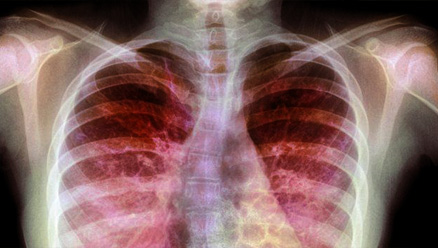

Si bien la remoción de células muertas es un proceso fisiológico propio de organismos sanos, en el caso de pacientes que padecen fibrosis quística la eferocitosis no funciona adecuadamente en células epiteliales ni en células del sistema inmune. "En el epitelio pulmonar de una persona sana no se encuentran células muertas porque son removidas rápidamente, sin embargo, en pacientes con fibrosis quística y debido a varias causas, algunas ligadas a la mutación, y otras a la inflamación, hay gran cantidad de células muertas sobre todo en las vías respiratorias por lo que las bacterias tienen muchos lugares donde unirse", explicó Kierbel.

Según la investigadora, la infección por P. aeruginosa es la principal causa de muerte de los pacientes con fibrosis quística. Estas bacterias, una vez que ingresan al organismo, forman biofilms que son muy resistentes a los antibióticos y los pacientes terminan muriendo a causa del daño pulmonar provocado por la permanencia de esos biofilms a lo largo de los años.

En la fibrosis quística P. aeruginosa infecta hasta más de un 90% de pacientes adultos, elevando la mortalidad y el deterioro pulmonar. Esta bacteria puede sobrevivir y persistir por algunas décadas en el tracto respiratorio de los pacientes con Fibrosis Quística.